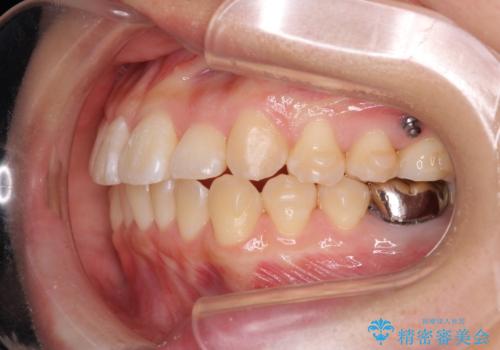

正中のズレ、引っ込んだ前歯の矯正

- 噛んだ時の前歯正中のズレ、引っ込んでいる前歯を治したい。と矯正治療を希望され来院されました。

左上2の前歯はスペースが足りないため、後方に引っ込んでしまっている状態です。

マウスピース矯正システムインビザラインで歯の後方移動、咬合関係の修正を行ったのち、引っ込んでいる左上2をワイヤーを用いて短時間で引き出す治療計画としました。

部分ワイヤー矯正を行なったことで約3ヶ月という短期間で前歯を綺麗に並べることができました。